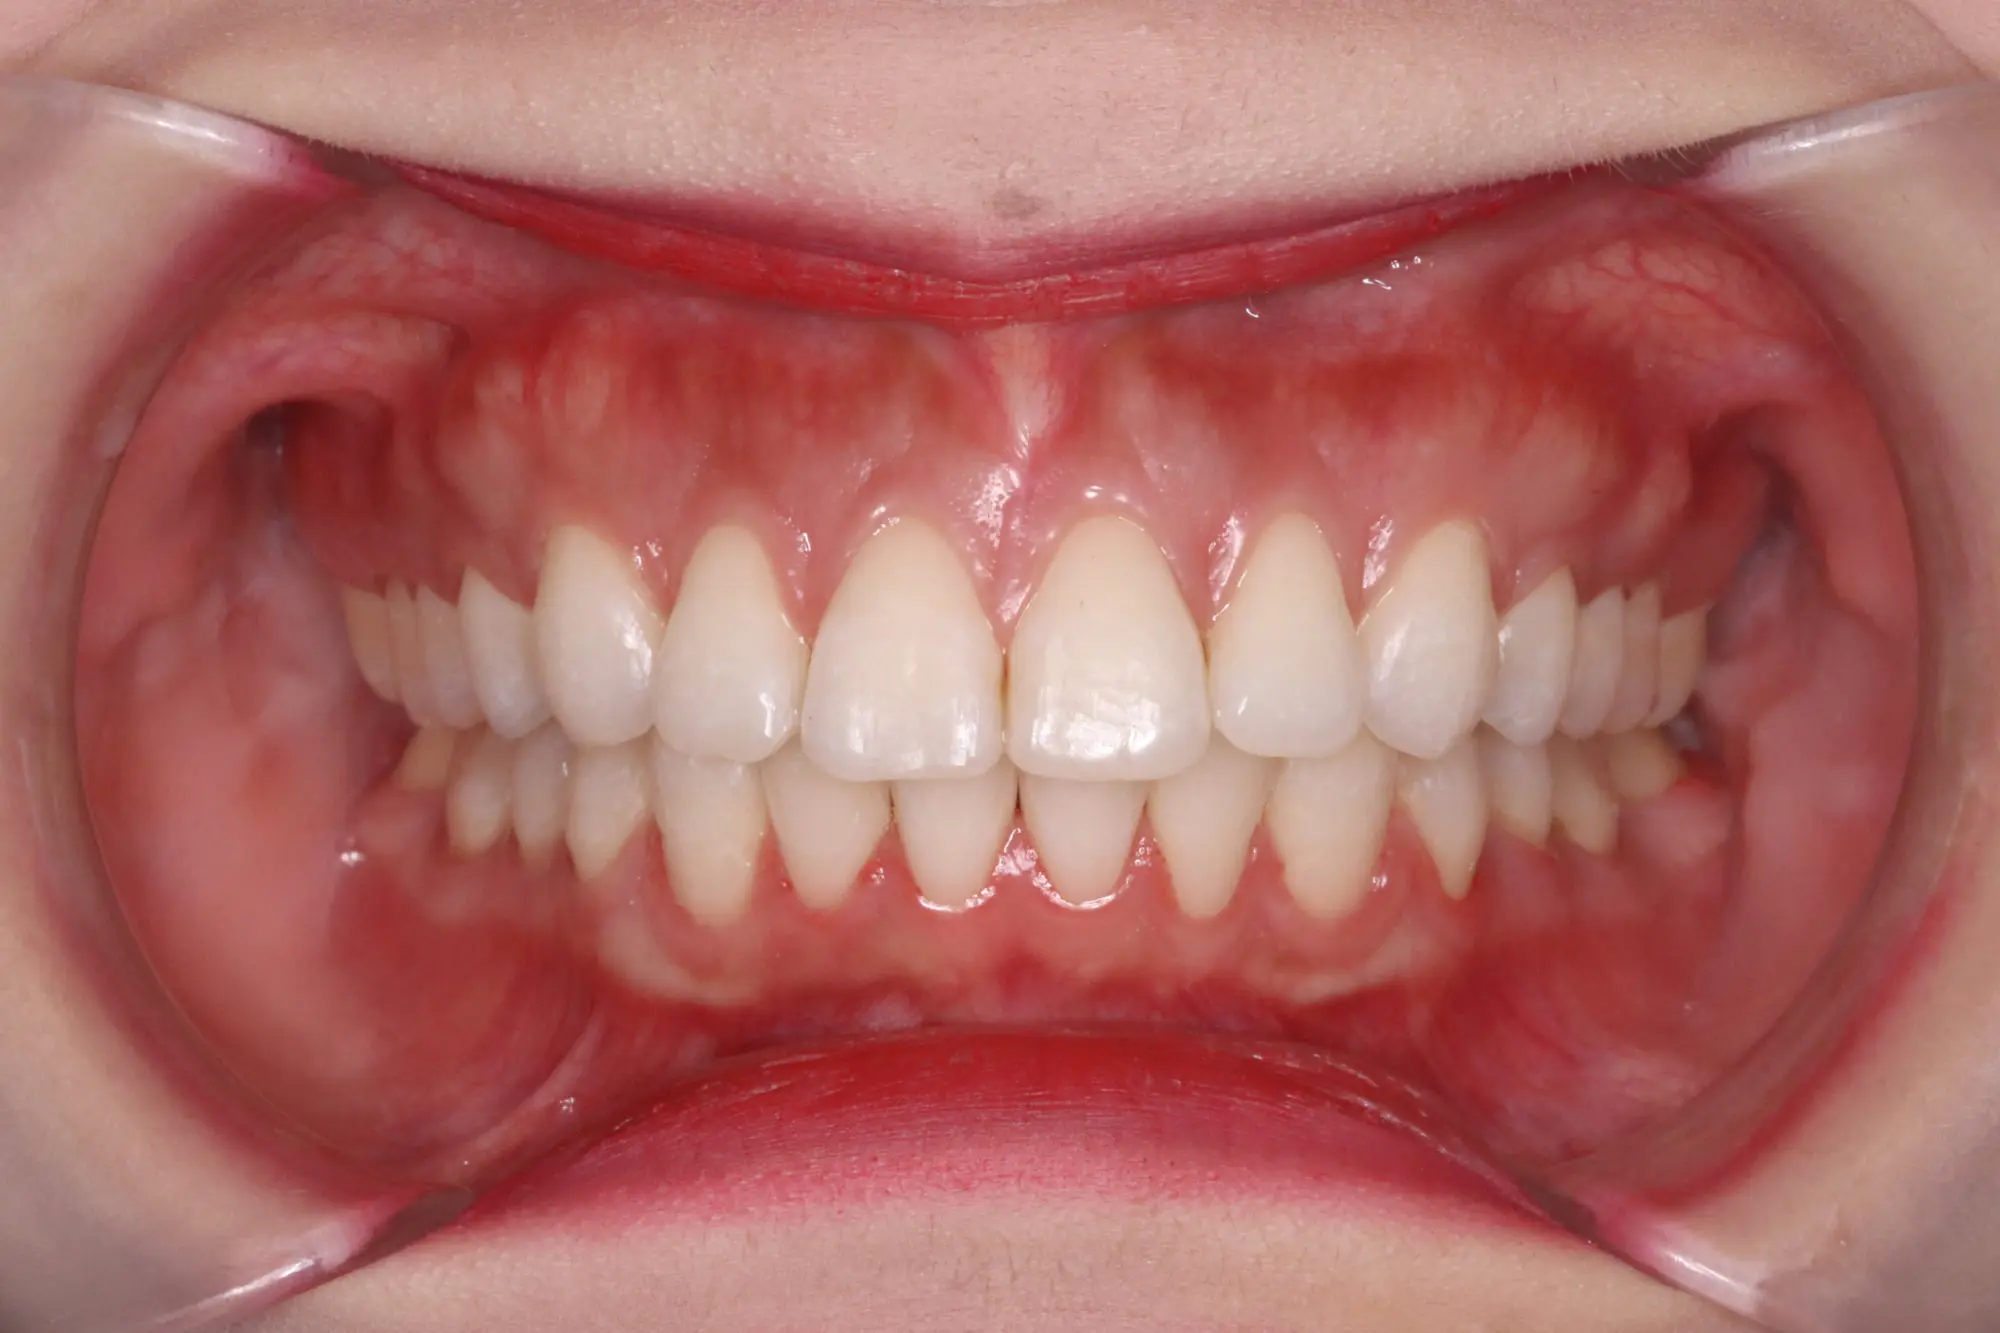

Before

After